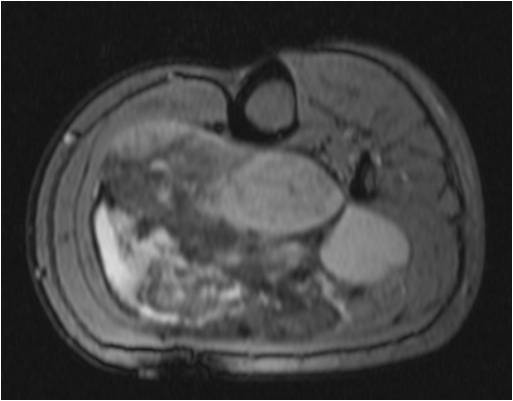

On radiographs, Low Grade Fibromyxoid Sarcoma presents as a discrete mass with soft tissue density without mineralization. MRI shows a well circumscribed heterogeneous mass, primarily hypo or isointense to muscles on T1-weighted image. The majority of tumors demonstrate heterogeneous signal intensity on T2-weighted images, correlating with the histological characteristics of low grade fibromyxoid sarcoma. Although 48 % of the patients demonstrate hyperintense signal and the rest of patients present admixed of hypo and Isointense signals (Fig. 1-5).

Fig. 1 & 2: MRI Axial (Fig. 1) and Coronal T1-weighted MR image (A) of a Low Grade Fibromyxoid Sarcoma demonstrates a well-defined mass of intermediate signal intensity with muscle and central areas of hypo intensity in the posterior compartment of the calf.

Fig. 3-5. MRI Axial (Fig. 3) and Coronal (Fig. 4) T2 –weighted fat-suppressed image heterogeneously high signal intensity areas admixed with hypo and isointense areas. T1-weighted post contrast fat-suppressed images (Fig. 5) show heterogeneous signal and enhancement within the tumor.